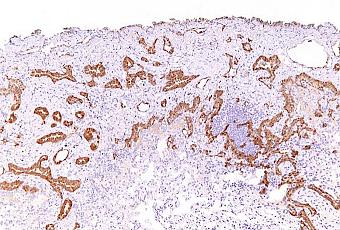

Mésothéliome Epithéloïde Malin

Source iconographique: https://commons.wikimedia.org/wiki/File:Malignant_epithelioid_mesothelioma_-_calretinin_-_intermed_mag.jpg